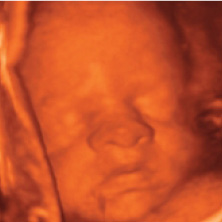

Your baby weighs around 2.2lbs now, and is around 37.6cm long and perfectly formed.

Your baby is continuing to pad out, and is gaining weight quickly, and although they look like a perfect little baby already, they will put on quite a few more pounds before birth.